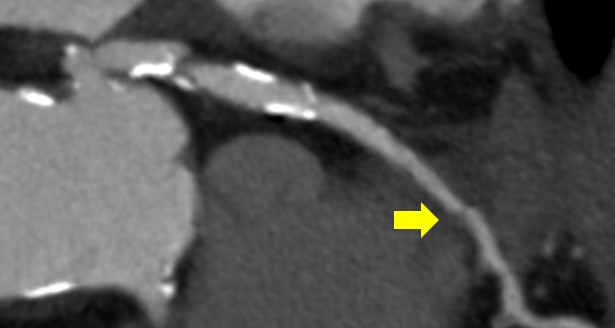

下記の画像は、Ascend Eliteと以前のワイドカバレッジCTでアブレーション用の造影CTを行った症例の比較画像になります。当院のAfに対する術前CT検査において、従来の装置では3心拍以上撮影しておりました。その理由として、当院では冠動脈評価も同時に行うため心拍数が偶然伸びたところを撮影できれば良い画像が得られるだろうという理由で、3心拍以上撮影を行っておりました。

左側の従来のSSF2.0を使用していなかった際の画像は3心拍以上のvolumeデータを使用して再構成を行っているにも関わらず大動脈弁がぶれてしまっています。右側のAscend Eliteでは大動脈弁をしっかり描出できています。この画像はCT装置導入二日目にして得られたため、SSF2.0が冠動脈だけでなく弁にも有用であることが証明できた症例となりました。

Ascend_ayase02.png同一患者における画像の比較

(左:従来の検査データ)(右:Ascend Elite)